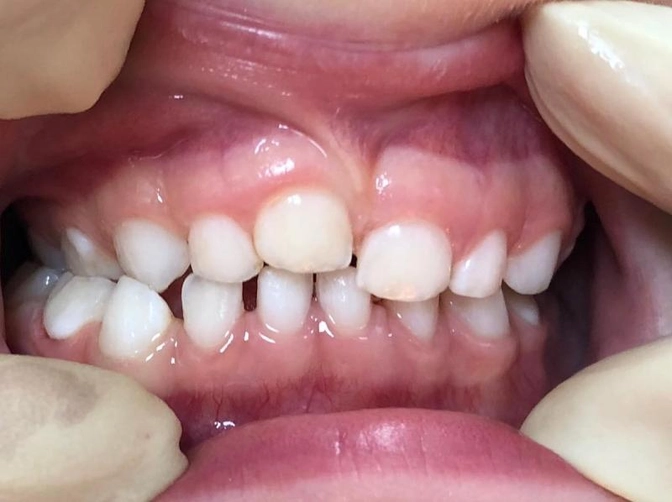

Вколоченный вывих молочного зуба.

Один центральный зуб выше другого.

Итак, девочке 4,5 года.

Когда ей было 2, она неудачно упала и ударилась зубами.

Один из них частично вколотился в десну.

Называется это - вколоченный вывих.

Так случилось и в данном случае.

Сейчас прогноз более, чем благоприятный.